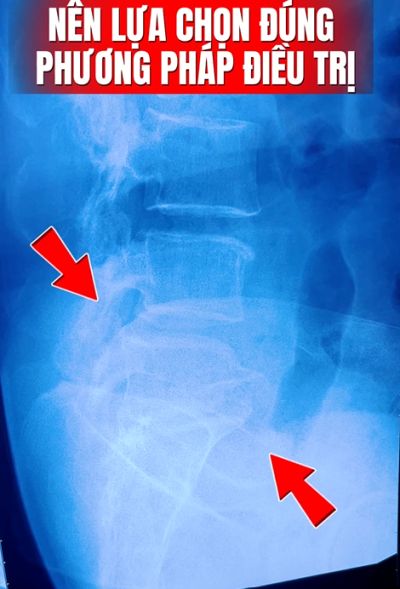

Thoát vị đĩa đệm cột sống cổ (Cervical Disc Herniation) và cột sống thắt lưng (Lumbar Disc Herniation) là những bệnh lý cơ xương khớp mang tính thời đại. Bản chất của bệnh lý này là sự suy giảm cấu trúc bao xơ, khiến nhân nhầy (Nucleus Pulposus) thoát vị ra ngoài, gây chèn ép cơ học trực tiếp lên rễ thần kinh và tủy sống.

Tại Trung Tâm Vật Lý Trị Liệu Tiền Giang, với nền tảng chuyên sâu trong lĩnh vực phục hồi chức năng, chúng tôi mang đến giải pháp điều trị toàn diện: Không dùng thuốc – Không phẫu thuật – Giải nén cột sống tầng sâu.